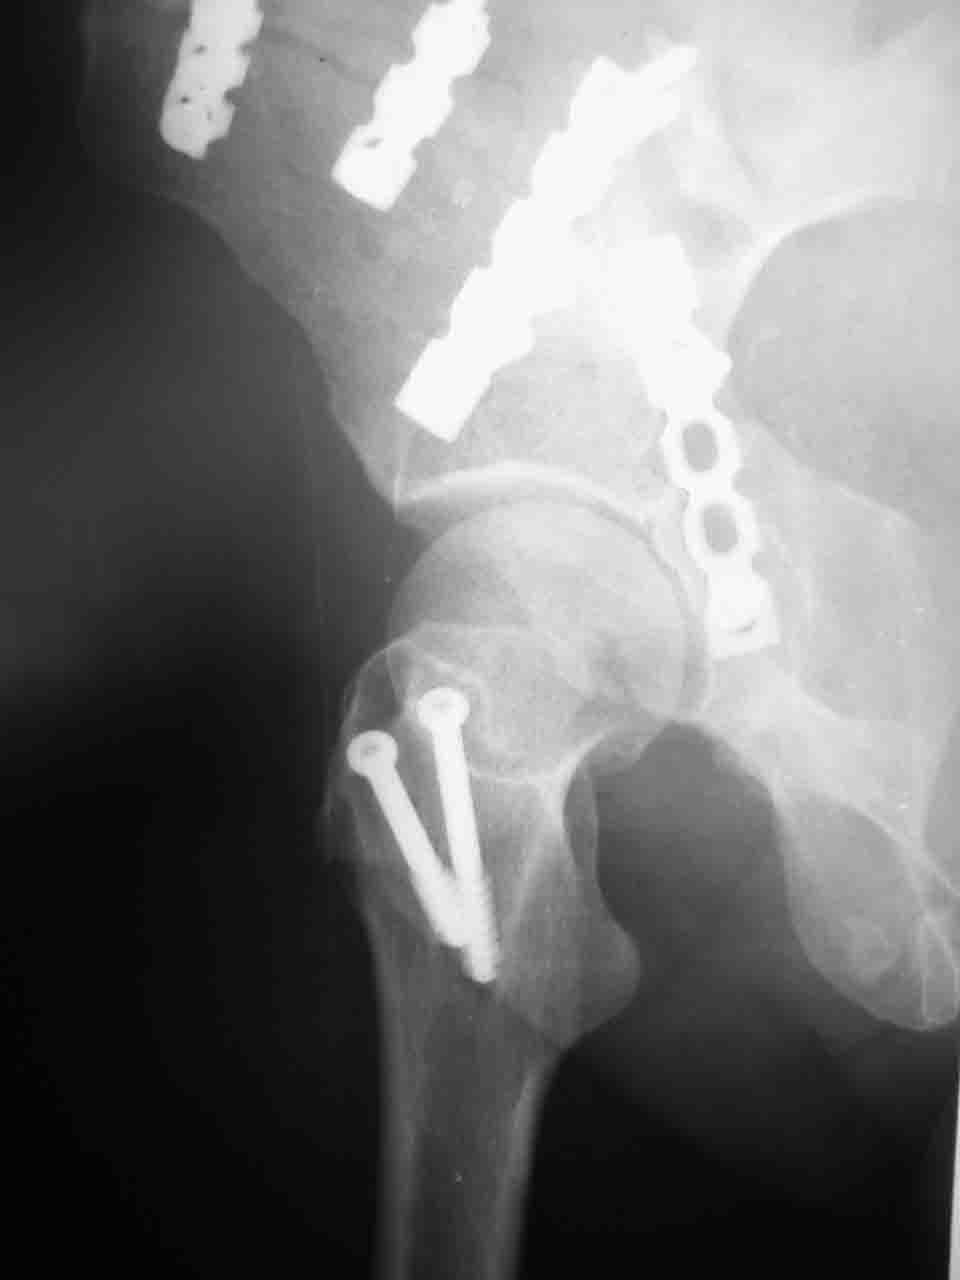

Вопрос доступа к вертлужной впадине при остеосинтезе задача не простая. Конечно, у Летурнеля и Тайла всё давно описано, нам остается только брать на вооружение. Но сами понимаете, что не бывает двух одинаковых ситуаций, поэтому в каждом случае вопрос решается сугубо индивидуально. Наша главная цель - восстановить анатомию с нанесением минимальной дополнительной травмы тазобедреннному суставу, думаю с этим никто не поспорит. Расширенный илиофеморальный доступ уж слишком травматичен (как сказал один коллега "таз лежит отдельно, больной отдельно").Стоит ли делать из пациента анатомический препарат для того чтобы легче ориентироваться. Да и нужно ли собирать всю "мозаику"? Мы применяли при таких операциях своеобразную операционную хитрость - сначала устраняли грубое смещение крыла под гребнем с фиксацией так называемой "плавающей" пластиной (временно фиксированной на двух винтах)- доступ или продлевали боковой, или делали небольшой дополнительный разрез над гребнем. Это позволяло устранить грубое смещение и захождение отломков тела повздошной кости, что значительно облегчало репозицию и остеосинтез впадины над сводом. Основное внимание конечно же уделяли нагружаемому задне-верхнему отделу. Сообщите ваш адрес, пришлю схемы и рентгенограммы.

Комбинированные доступы - хорошая альтернатива, меньший процент осложнений, но я заметил , что без сбора *мозаики* безымянной кости сложно отрепонировать переднюю колонну, а с нерепонированной передней колонной невозможно анатомично собрать заднюю колонну и соотв. фрагменты стенки - так.что все равно открывать придется широко. Поэтому выбирая комбинированный

подход, передний доступ должен был бы быть продлен до задней трети крыла безымянной кости, а задний - практически до того же уровня, оставляя 6-7 см мостик. При этом вместо одного послеоп. рубца у больного остаются два сравнительно длинных.